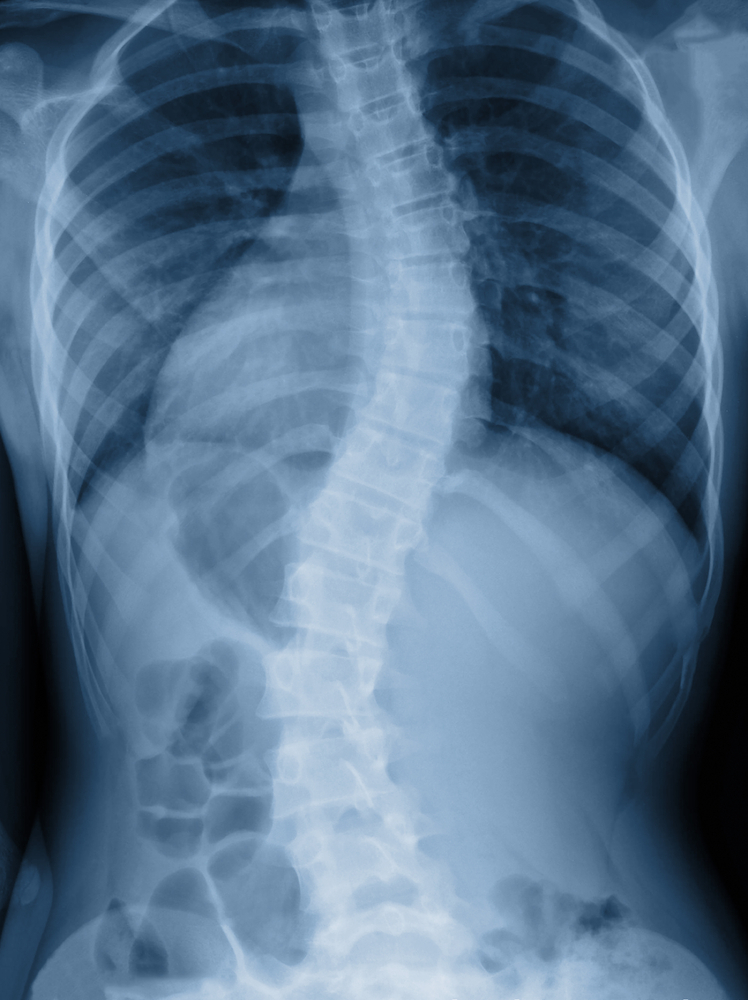

جنف بالعامود الفقري ت م ن

المريضة ت م ن مقيمة ,  تبلغ من العمر 14 عاماً ، طالبه، تسكن مع والدتها في بيت إيجار ، تعاني من الآم شديدة بالعامود الفقري مع تشوهات وتزداد سوء مع مرور الوقت و هي  بالحاجة الى إجراء عملية جراحية  تبلغ التكلفة الاجمالية  180000 ريال فقط، ويضاف اليها النسبة التشغيلية 10%  يصبح المبلغ 198000  وهي بحاجه لدعم والمساعدة  .